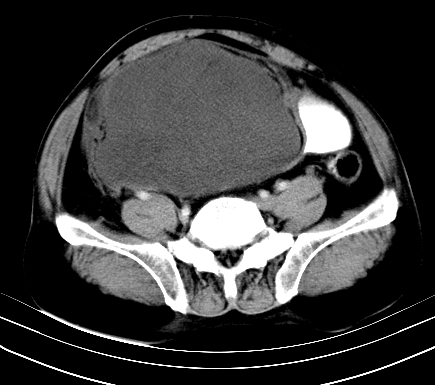

标题: CT19729B:男,74岁,因腿疼就诊,查体触腹部肿物,

增强扫描

重建

【ct表现】

1、肿块巨大,往往位于腹膜后,长大后才引起症状而就诊;那么位于腹膜后的肿瘤80%为恶性肿瘤。

2、实性肿瘤,增强扫描轻度不均强化,实性肿瘤一般不是好东西。

3、肿瘤边缘似见少许脂肪样密度。

4、腹膜后未见肿大淋巴结,但肿瘤于临近的肠管及组织接触紧密。

【诊断】

腹部占位,考虑位于腹膜后的恶性肿瘤,脂肪肉瘤(实体型)可能性大。

术后病理结果:腹膜后脂肪肉瘤。